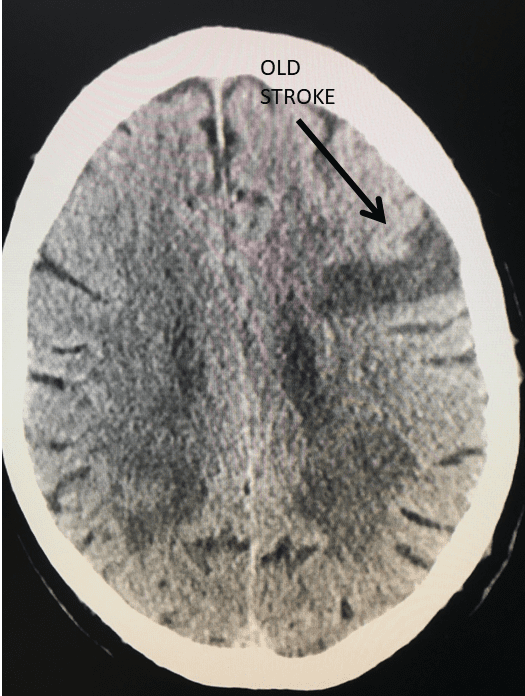

Brain:

Brain Metastasis

Author: Michael Brisman M.D., F.A.C.S., Read More!